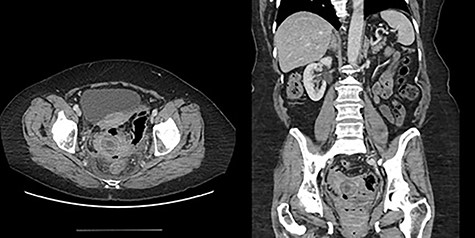

The second patient is a 69-year-old female who presented to the emergency room with complaints of obstipation and abdominal pain. She reported a 2-month history of intermittent sudden onset abdominal pain accompanied by abrupt bowel movement and nausea. At the time of presentation, she reported constipation for 5 days; she had tried fiber and suppositories without relief. Her past medical history included hypertension and irritable bowel syndrome. She had no prior abdominal surgeries or colonoscopies. Upon evaluation, she was afebrile and hemodynamically stable. Her abdomen was softly distended with localized left lower quadrant tenderness and no peritoneal signs. Her rectal exam was unremarkable. She had a mild leukocytosis of 12.9 thou/cmm. Abdominopelvic CT with intravenous contrast was obtained and revealed inflammatory stranding consistent with acute diverticulitis with a lamellated intraluminal mass in the sigmoid colon in the region of inflammation as well as pneumobilia (Fig. 4); these findings led to the diagnosis of a gallstone impaction with resulting large bowel obstruction.